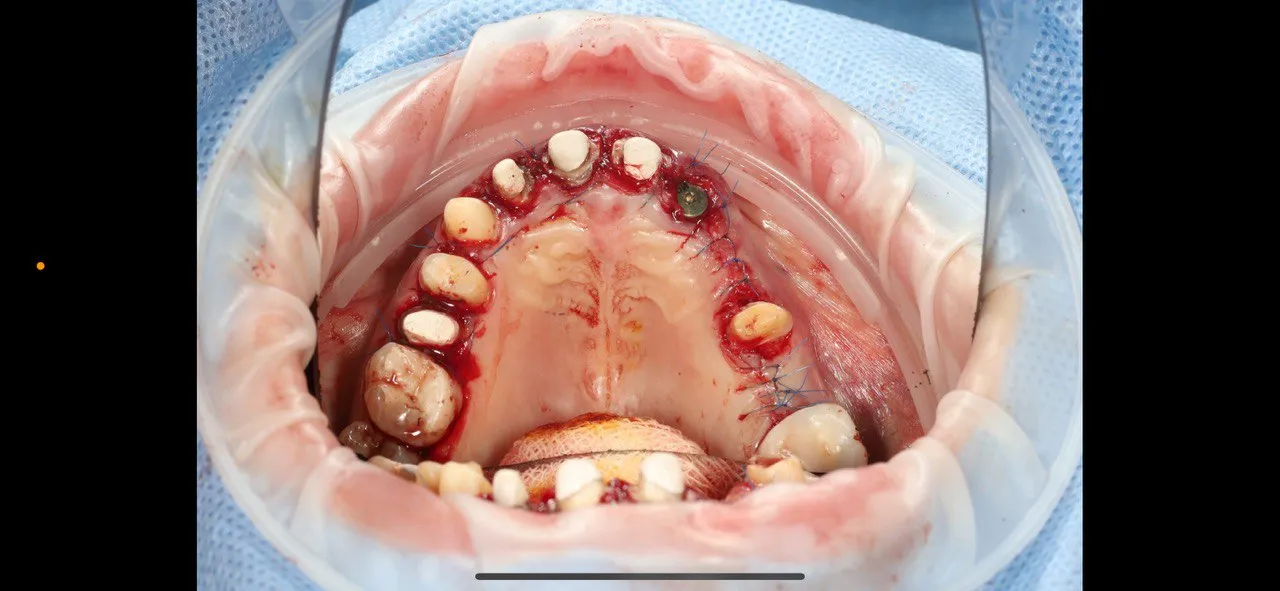

Full-Arch Implant Rehabilitation

All-on-4 surgical guide for complete upper arch restoration